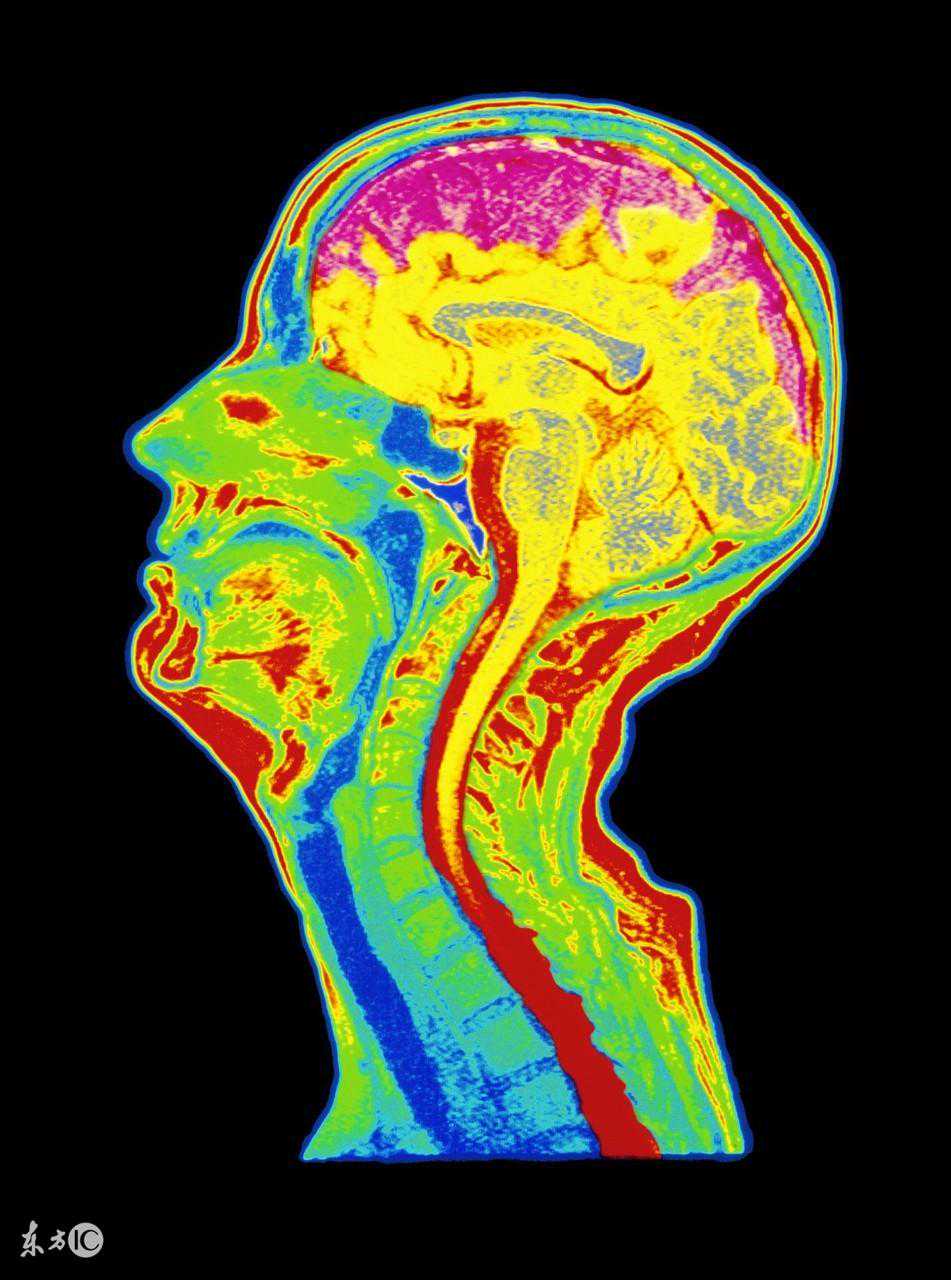

脑萎缩最主要的致病因素是脑血管长期慢性缺血,导致红细胞变形能力下降,微血管的有效血液灌注不足,脑组织处于慢性缺血、缺氧状态,脑细胞形态及功能受到影响,即形成脑萎缩。其病理变化可见脑回变平,脑沟增宽,脑室脑池扩大,脑重量减轻。多为大脑皮质萎缩。因萎缩部位和涉及范围不同又可分为局限性和弥漫性脑萎缩,大脑、小脑、橄榄体、桥脑萎缩,皮质型和中央型萎缩。